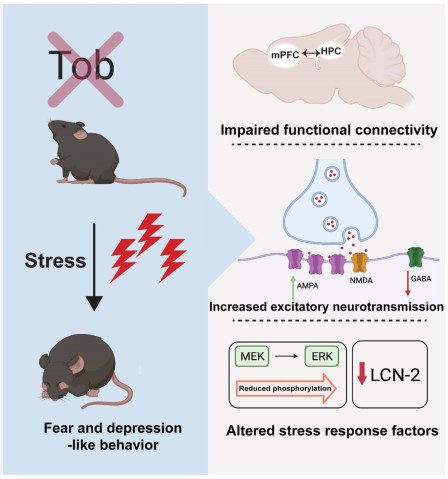

Their conclusion that this gene is linked to anxiety, fear, and depression was drawn from several different experiments. First, the researchers exposed mice to stress and, as expected, saw the Tob protein levels increase. They then used mice which had been born without a Tob gene and found an increase in depression, fear, and anxiety. For example, when a mouse with the Tob gene was placed in a bucket of water, they would swim and try to escape. However, a mouse without the Tob gene simply floated. This lack of will to fight a difficult situation is one way that researchers determine that an animal is depressed.

What’s more, the mice without the Tob gene didn’t seem to learn. Dr. Youssef explained that when mice are put day-after-day in a place which evokes fear memory, they normally learn that it isn’t so bad and stop being as frightened. But those without the Tob gene still showed increased levels of fear observed as freezing, even after several days.

The researchers then teamed up with OIST’s former PhD student Dr. Hiroaki Hamada from the Neural Computational Unit. Through an MRI, they found that the connectivity between two key places regulating brain’s stress resilience was altered when the Tob gene was removed—the hippocampus and the pre-frontal cortex. From there, the researchers decided to look at the specific role that the gene plays within the hippocampus. They took mice without the Tob gene and injected this gene into the hippocampus, while leaving it nonexistent in other parts of the body. The level of fear and depression returned to normal, but the mice still had increased anxiety. The researchers then did the opposite—they created a mouse that had no Tob gene in the cells in the hippocampus but had it in the cells in the rest of the body. In this case, they found that the mice had normal levels of anxiety but increased fear and depression.

“We’ve concluded that the Tob gene within the hippocampus suppresses fear and depression,” explained Dr. Youssef. “But the suppression of anxiety must be regulated by another part of the brain.”

Next, researchers from OIST’s former Brain Mechanisms for Behavior Unit measured the function of the neurons within the hippocampus of the mice without the Tob gene. They found that excitation was increased, while inhibition was decreased, suggesting that the overall balance was impacted, which would impact the behavior of the mice.

Finally, the researchers conducted molecular analyses after exposing the mice to stress. Interestingly, they found that expression didn’t immediate change with stress. But, 15 minutes after exposing the mice to stress, there were changes. Other genes and proteins were impacted if the Tob gene was deleted. This suggests that the Tob gene likely has multiple direct and indirect impacts.